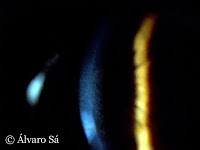

Apresentava ceratocone (patologia frequente da córnea, caracterizada por uma diminuição progressiva da sua espessura na região central ou paracentral, com consequente deformação e diminuição acentuada da visão).

Fotografias tiradas na primeira consulta. Observamos a deformação da córnea (adquiriu a forma de um cone) e as estrias de Vogt (pregas verticais paralelas na zona mais fina do cone, que correspondem a linhas de tensão do estroma corneano).